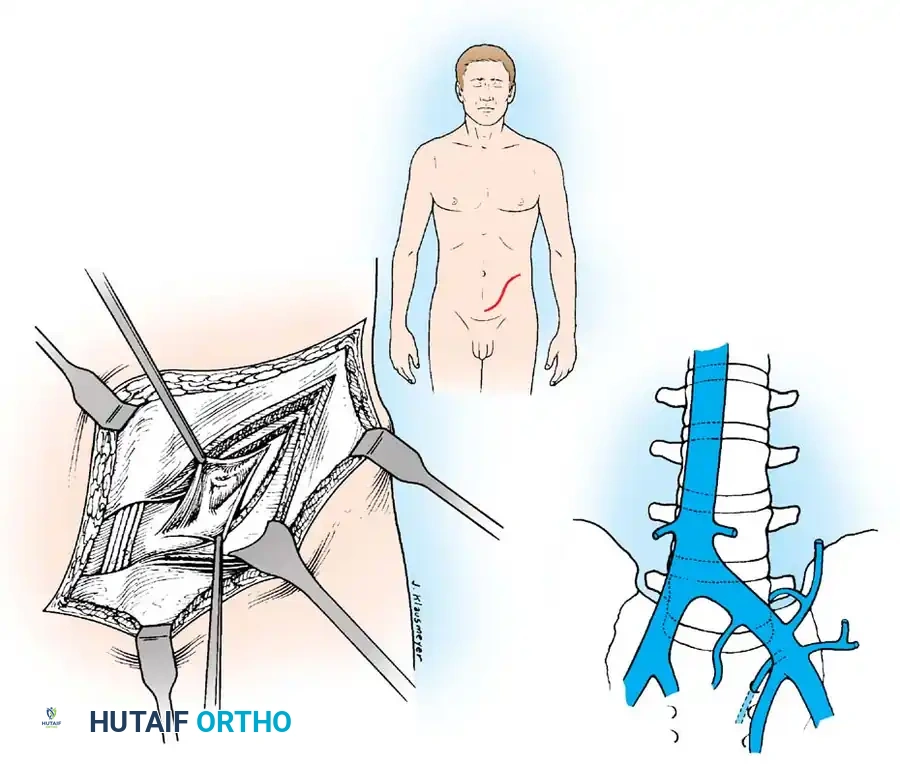

Lumbosacral Junction (L5–S1)

Expose the L5 and S1 vertebrae through an extraperitoneal approach.

* Make a "lazy-S" incision starting in the midline (midway between the symphysis pubis and the umbilicus) and curving laterally to a point midway between the iliac crest and the lowest rib.

* Divide the abdominal musculature (external oblique, internal oblique, transversus abdominis) in line with the incision.

* Sweep the peritoneum medially off the lateral abdominal wall, exposing the left psoas muscle and the lumbosacral spine.

Vascular Management at the Bifurcation:

The approach to the L5-S1 disc space is dictated by the anatomic level of the aortic bifurcation.

* High Bifurcation: The safest approach is directly between the common iliac vessels. The primary vessels encountered here are the middle sacral artery and vein, which must be cauterized and divided.

* Low Bifurcation: The approach must be made lateral to the aorta, vena cava, and common iliac vessels. To safely mobilize the left common iliac vein to the right, you must meticulously isolate, ligate, and divide the iliolumbar and ascending lumbar veins. If a higher exposure is needed, ligate the 4th and 5th lumbar vessels.